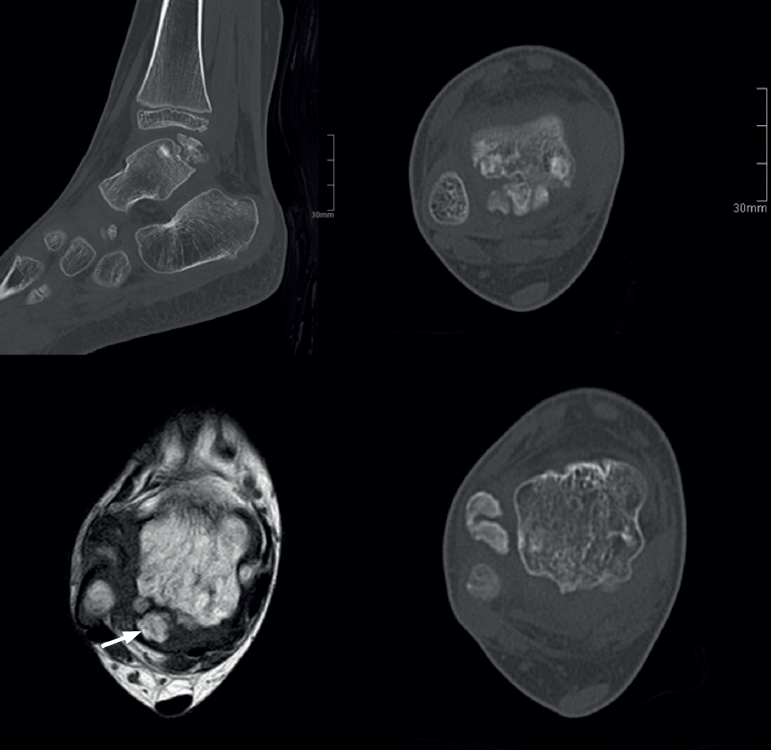

Para diferenciar una fractura de un os trigonum se recurrirá no solo a radiología convencional anteroposterior lateral y de la mortaja, sino a proyecciones oblicuas y de Broden, y preferentemente a la TC(43).

En adultos (Figuras 6 y 7), se cita como causa de pinzamiento doloroso en la cámara posterior del tobillo(50), aunque también como causa de impingement anterior(51), o confundirse con un osteocondroma a pesar de sus diferencias histológicas. Mientras el osteocondroma reproduce una arquitectura similar a la de la placa de crecimiento, la displasia epifisaria hemimélica muestra en su cubierta cartilaginosa áreas con acúmulos de condrocitos y pequeñas áreas de cartílago calcificado no reabsorbido(52). Por otra parte, la presencia de osteocondromas en la parte posterior del astrágalo es muy rara. En una serie de 7 casos en los que se produjo rotura a través del pedículo en relación con ejercicio físico, Carpintero et al. no señalan ninguna en esta localización(53).

Algunos autores lo han relacionado también con una infección neonatal(56). El aspecto radiológico puede aparentar una fractura y así relacionarse con microtraumatismos repetidos en la infancia o inestabilidad(57), aunque su principal característica es la articulación del fragmento posterior con el calcáneo , llegando a formar una prolongación en consola (Figura 8).

En su evolución suele presentar dolor, grados variables de afectación articular y edema óseo visible en los estudios por RM(10) que lleva a plantear tratamientos quirúrgicos en la serie de 4 casos de Rammelt et al.(58).

El tratamiento del dolor producido por un talus bipartitus, síndrome de Trevor o un os trigonum de gran tamaño no está sistematizado, al registrarse casos esporádicos y series muy cortas. Desde tratamiento conservador a resección artroscópica o abierta de fragmentos, hasta la artrodesis subastragalina en muchos casos por la inestabilidad creada(58,59).